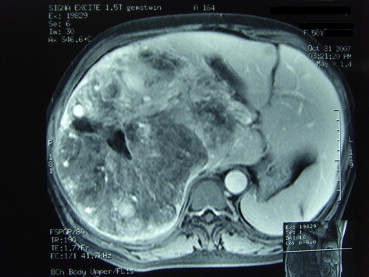

All patients had USG examination. Fifty-eight patients underwent both plain CT and intravenous contrast-enhanced CT examination (Fig. 1) and 35 patients underwent MRI examination (Fig. 2). After we analyzed our data, we were able to suggest the diagnostic features of hepatic angiomyolipoma (Table 2). Unfortunately, using these criteria, only 23% of patients with hepatic angiomyolipoma could be diagnosed before treatment.

MRI showing peripheral angiomatous component, a fatty component and prominent ...

Figure 2.

MRI showing peripheral angiomatous component, a fatty component and prominent central vessels.

● MRI - presence of hypointensity or hyperintensity on T1-weighted imaging and hyperintensity on T2-weighted imaging

Multiple modalities of tests have been used to aid in the diagnosis of hepatic angiomyolipoma. Laboratory tests, such as viral markers for hepatitis, tumor markers, and liver function, have been negative or have not been proven to be specific or helpful in the diagnosis of hepatic angiomyolipoma. Identification of fat within a liver lesion can be critical in characterization of the lesion. Radiographically, hepatic angiomyolipoma has the characteristic imaging features of fatty tissue, yet the diagnosis is only correctly suggested in a minority of cases. Although a combination of USG, CT, MRI is able to increase the accuracy in preoperative diagnosis, hepatic angiomyolipoma usually shows non-typical patterns in imaging studies.7; 8; 9 ;  10 The difficulty in imaging diagnosis occurs because of the wide variation in the proportions of vessels, muscles, and fatty tissue in different tumors. Consequently, hepatic angiomyolipoma is difficult to diagnose on imaging studies alone. USG is currently the first screening method for liver tumors, but USG findings of most liver tumors are nonspecific. As hyperechoic liver nodules cannot be characterized by USG, subsequent examination using CT, MRI, or even fine-needle aspiration cytology (FNAC) is necessary.18 CT, and MRI typically demonstrate the fat component and prominent central vessels. At CT scan, hepatic angiomyolipoma has been reported to consist of two parts: a peripheral angiomyomatous component with soft-tissue attenuation and a fatty component with an attenuation value less than –20 HU.5; 6; 7 ;  8 MRI characteristics vary, depending on the proportion of intratumoral fat. Frequently, hepatic angiomyolipoma has a high fat content, with high signal intensity on T1-weighted images and a significant drop in signal intensity on fat-suppressed images.5; 6; 7 ;  8 Diagnosis using FNAC or biopsy is again difficult, because of the heterogeneity of the lesion. The smooth muscle cells are the only specific and diagnostic components of hepatic angiomyolipoma and are characteristically immunostained positive for HMB-45 and Melan-A. This portion of tissue may or may not be sampled. The definitive diagnostic tool remains the histopathologic examination of the surgically resected specimen, coupled with immunohistochemical staining.